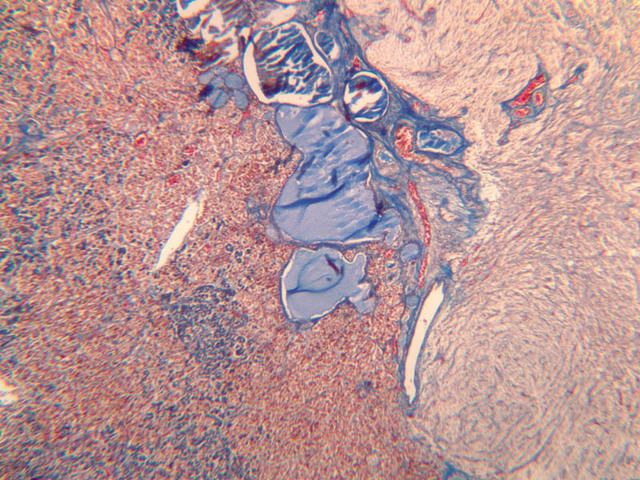

The adrenal gland (slide B-59, H&E [2.5x-labeled, 10x-labeled, 20x, 40x-labeled] [2.5x, 10x-labeled, 20x, 40x]; B-60, H&E [2.5x-labeled, 10x, 20x, 40x]; B-62, H&E [10x, 20x, 40x] [2.5x, 10x]) is a composite organ consisting of two functionally, structurally and embryologically different parts—an outer cortex and an inner medulla. Observe the gland at low power. Find the loosely organized tissue that comprises the medulla and the partially-separated columns of cells that make up the cortex. Scan the capsule and the tissue around it, looking for nerves and blood vessels. Study the pattern of cortical vasculature. In a pattern similar to that seen in the pars distalis of the pituitary, sinusoids run along the edges of columns or cords of cells. Owing to different arrangements of its constituent cells, the adrenal cortex has a layered appearance. From the capsule inward, these cortical layers are known as the zona glomerulosa, the zona fasciculata, and the zona reticularis.

The zona glomerulosa is located immediately beneath the capsule (B-60 adrenal gland, dog [10x, 20x] [20x, 40x]; B-59 [2.5x, 10x, 20x] [2.5x, 10x, 20x]). Its constituent cells are arranged in arcs or spheres, and, owing to their relatively small size, their nuclei appear to be close together. Cells of the zona glomerulosa secrete mineralocorticoids (e.g., aldosterone). The zona fasciculata consists of parallel columns or cords of cells that radiate toward the medulla and are separated by blood sinusoids (B-60 [2.5x, 10x, 20x, 40x]; B-62 [20x, 40x]). Owing to the extraction of lipids during histological processing, the cytoplasm of cells in the zona fasciculata appears highly vacuolated or "foamy". Cells of the zona fasciculata secrete glucocorticoids (e.g., hydrocortisone & cortisone) and some gonadocorticoids (weak androgens). The zona reticularis is the deepest cortical layer and lies adjacent to the medulla (B-60 [20x, 40x]; B-62 [20x, 40x]). It is characterized by irregular, interconnecting cords of cells which are separated by anastomosing capillary networks or sinusoids. Cells of the zona reticularis, which are smaller than those of zona fasciculata and do not contain as many lipid vacuoles, secrete gonadocorticoids and some glucocorticoids.